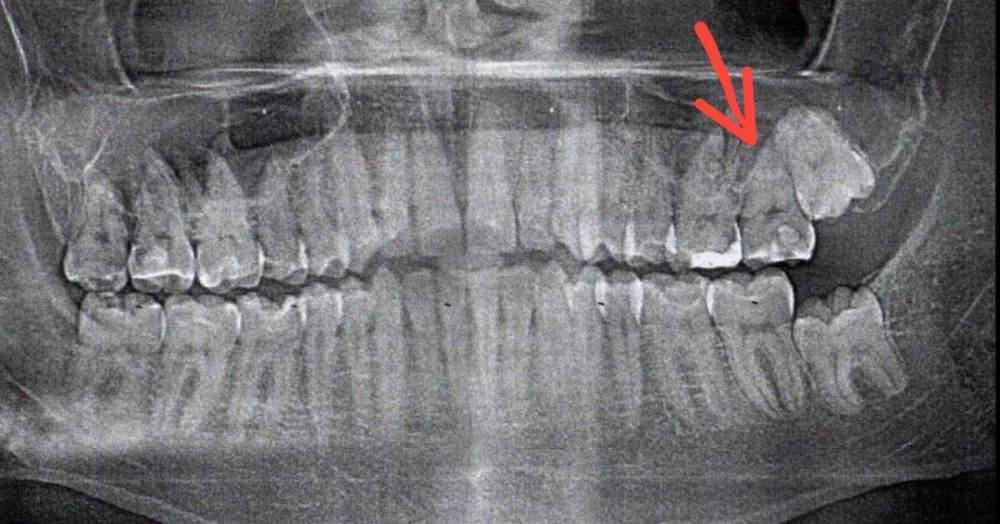

nikolas_magpies Опубликовано 14 декабря, 2023 Поделиться Опубликовано 14 декабря, 2023 Добрый день. У меня есть полис ДМС со стоматологией. В него НЕ входит лечение пораженного кариесом зуба, если он разрушен более, чем на половину (ИРОПЗ > 0,5). Появилась боль в 27 зубе. Обратился в поликлинику по ДМС. Врач стоматолог-терапевт сделал ортопантомограмму и отказал в лечение по ДМС, ссылаясь на разрушенность в 60%. Я с этим решением не согласен, по панорамному снимку видно разрушение явно меньше, чем на 50%, так как нижняя часть коронковой части зуба, которая светится белым цветом — является пломбировочным материалом, а остальная серая часть зуба до десны — является здоровым тканями зуба. Прикладываю сам снимок, подсчет площади старой пломбы и коронковой части зуба без пломбы. Подскажите, пожалуйста, как вы считаете, разрушен этот зуб более, чем на 50% или нет? Ссылка на комментарий